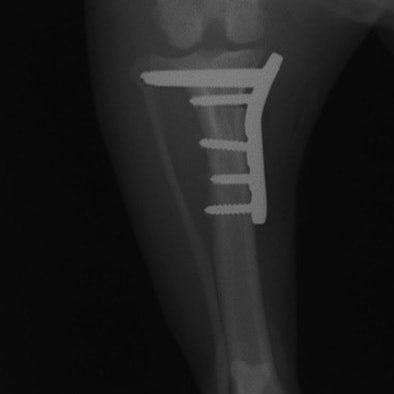

Fixin T字プレート使用して固定

・術後レントゲン

手術前TPA 28.4° が術後TPA 11.7° に矯正されました。

術前TPA計測

手術前

術後TPA計測

手術後

当院ではFixinmicroプレートを使用して小型犬のTPLO手術を実施しております。